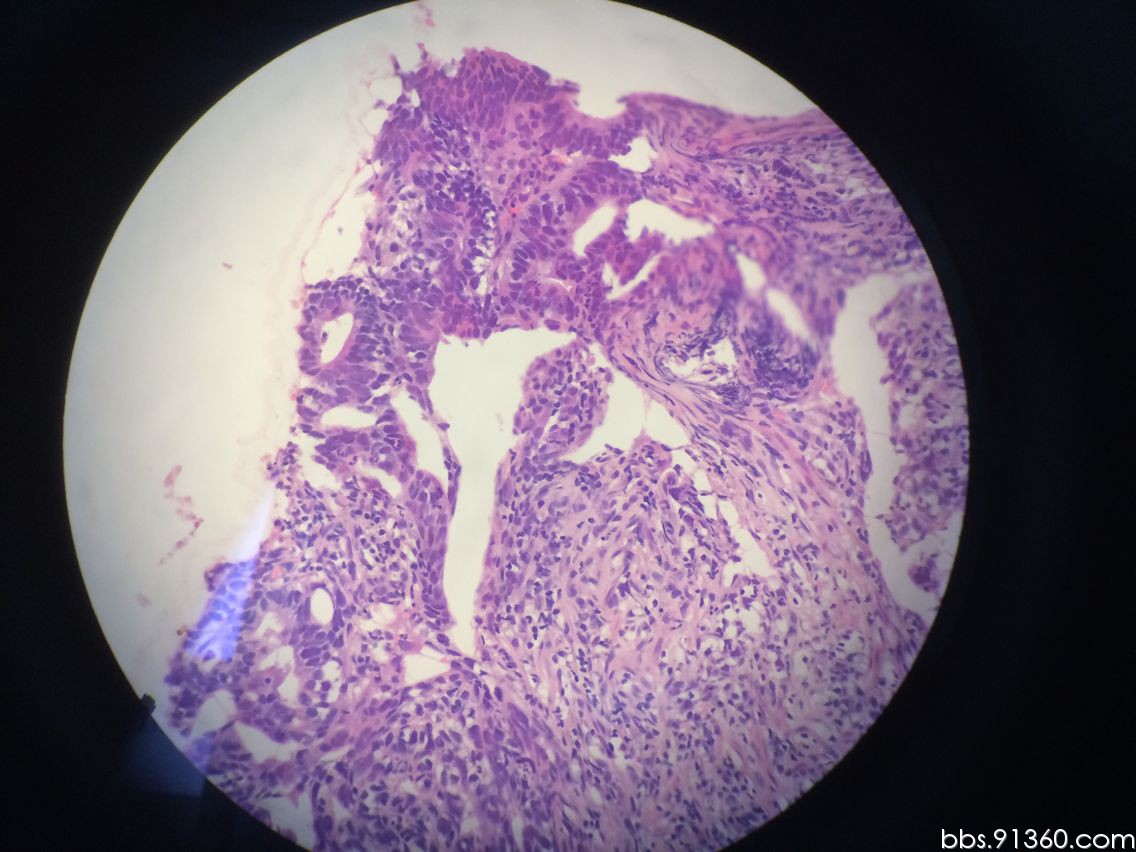

胃窦部黏膜组织活检镜下如图所示胃黏膜发生的有关病变的描述

图片尺寸512x384

胃窦部黏膜组织活检镜下如图所示胃黏膜发生的有关病变的描述错误的是

图片尺寸516x386